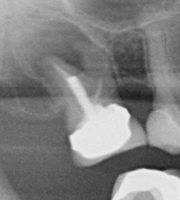

When our dentist for root canal performs a dental root canal treatment in Melbourne, it involves drilling a small hole into the tooth to gain access to the pulp chamber. Once this has been done, the root canal dentist will use specialised instruments to remove diseased and dead pulp tissue as well as clean out the pulp chamber and root canals. The root canals are thoroughly disinfected with antibacterial solutions and are prepared for special dental root canal fillings. The canal space will then be filled and a temporary or permanent filling will be used to seal the access hole.

03-06-01-2 03-06-01-4